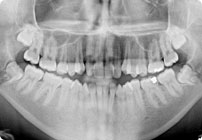

Antes

Despues

Caso: 11 años

Adolescente: Clase II

Mordida Cruzada Posterior

Sin extracción

Sin uso de expansores

6 alambres superiores

5 alambres inferiores

Sin uso de elásticos

Retenedores: Interior Fijo de TMA y Hawley en superior

Tiempo de tratamiento: 14 Visitas